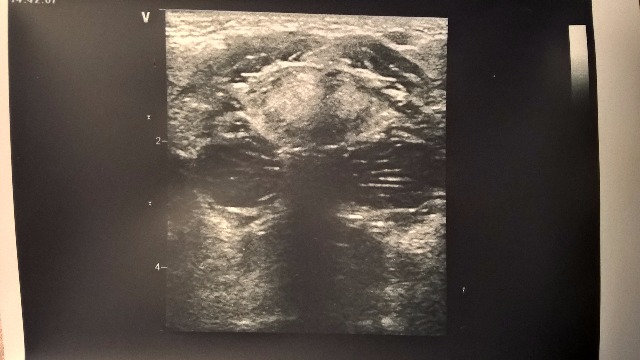

Интересные УЗ симптомы

Похоже на лицо инопланетянина